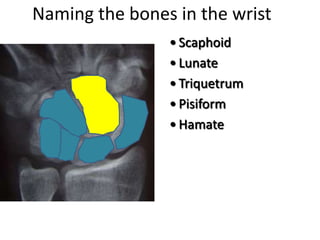

This document provides an overview of hand anatomy including:

- Naming the bones, joints, tendons, nerves and skin landmarks of the hand and wrist.